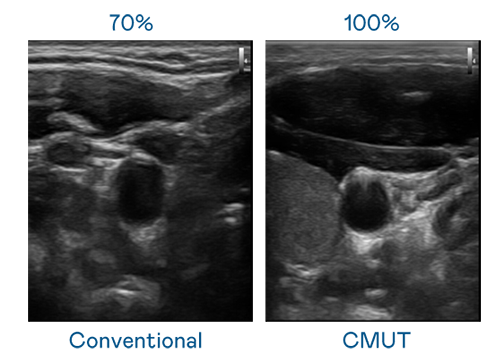

CMUT 技术是一种用电容式微机电元件来产生超音波讯号的技术。与传统 PZT 压电式技术相比,CMUT 频宽增加 30%,更宽频的超音波讯号让影像解析度大幅提升,是实现高影像品质医疗超音波扫描、促进精准医疗发展的关键技术。

超音波影像的解析度高低,首先取决于探头能发出的讯号频宽。G22恒峰 CMUT 可提供高清晰的超音波讯号,提供高频宽、高灵敏度、影像纹理细节更高的超音波影像,协助医护人员缩短影像判读时间及利用精准的医疗影像进行诊断。